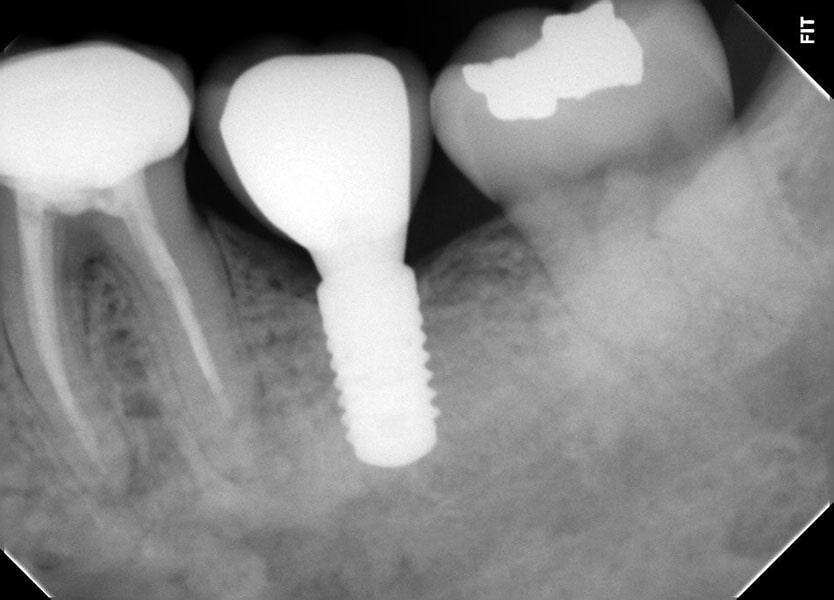

Implantes Dentales

Los implantes dentales son la solución ideal para reemplazar dientes perdidos de manera permanente y segura. Este tratamiento consiste en la colocación de un tornillo de titanio en el hueso maxilar, sobre el cual se fija una corona que imita la apariencia de un diente natural.